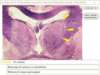

1) Blue – Pulvinar (Thalamus 2-Glass sections – slide 16)

2) Orange – Centromedian nucleus (Thalamus 2-Glass sections – slide 13)

3) Yellow – Red nucleus (Thalamus 2-Glass sections – slide 13)

4) Green – Mamillary body (Thalamus 2-Glass sections – slide 13)